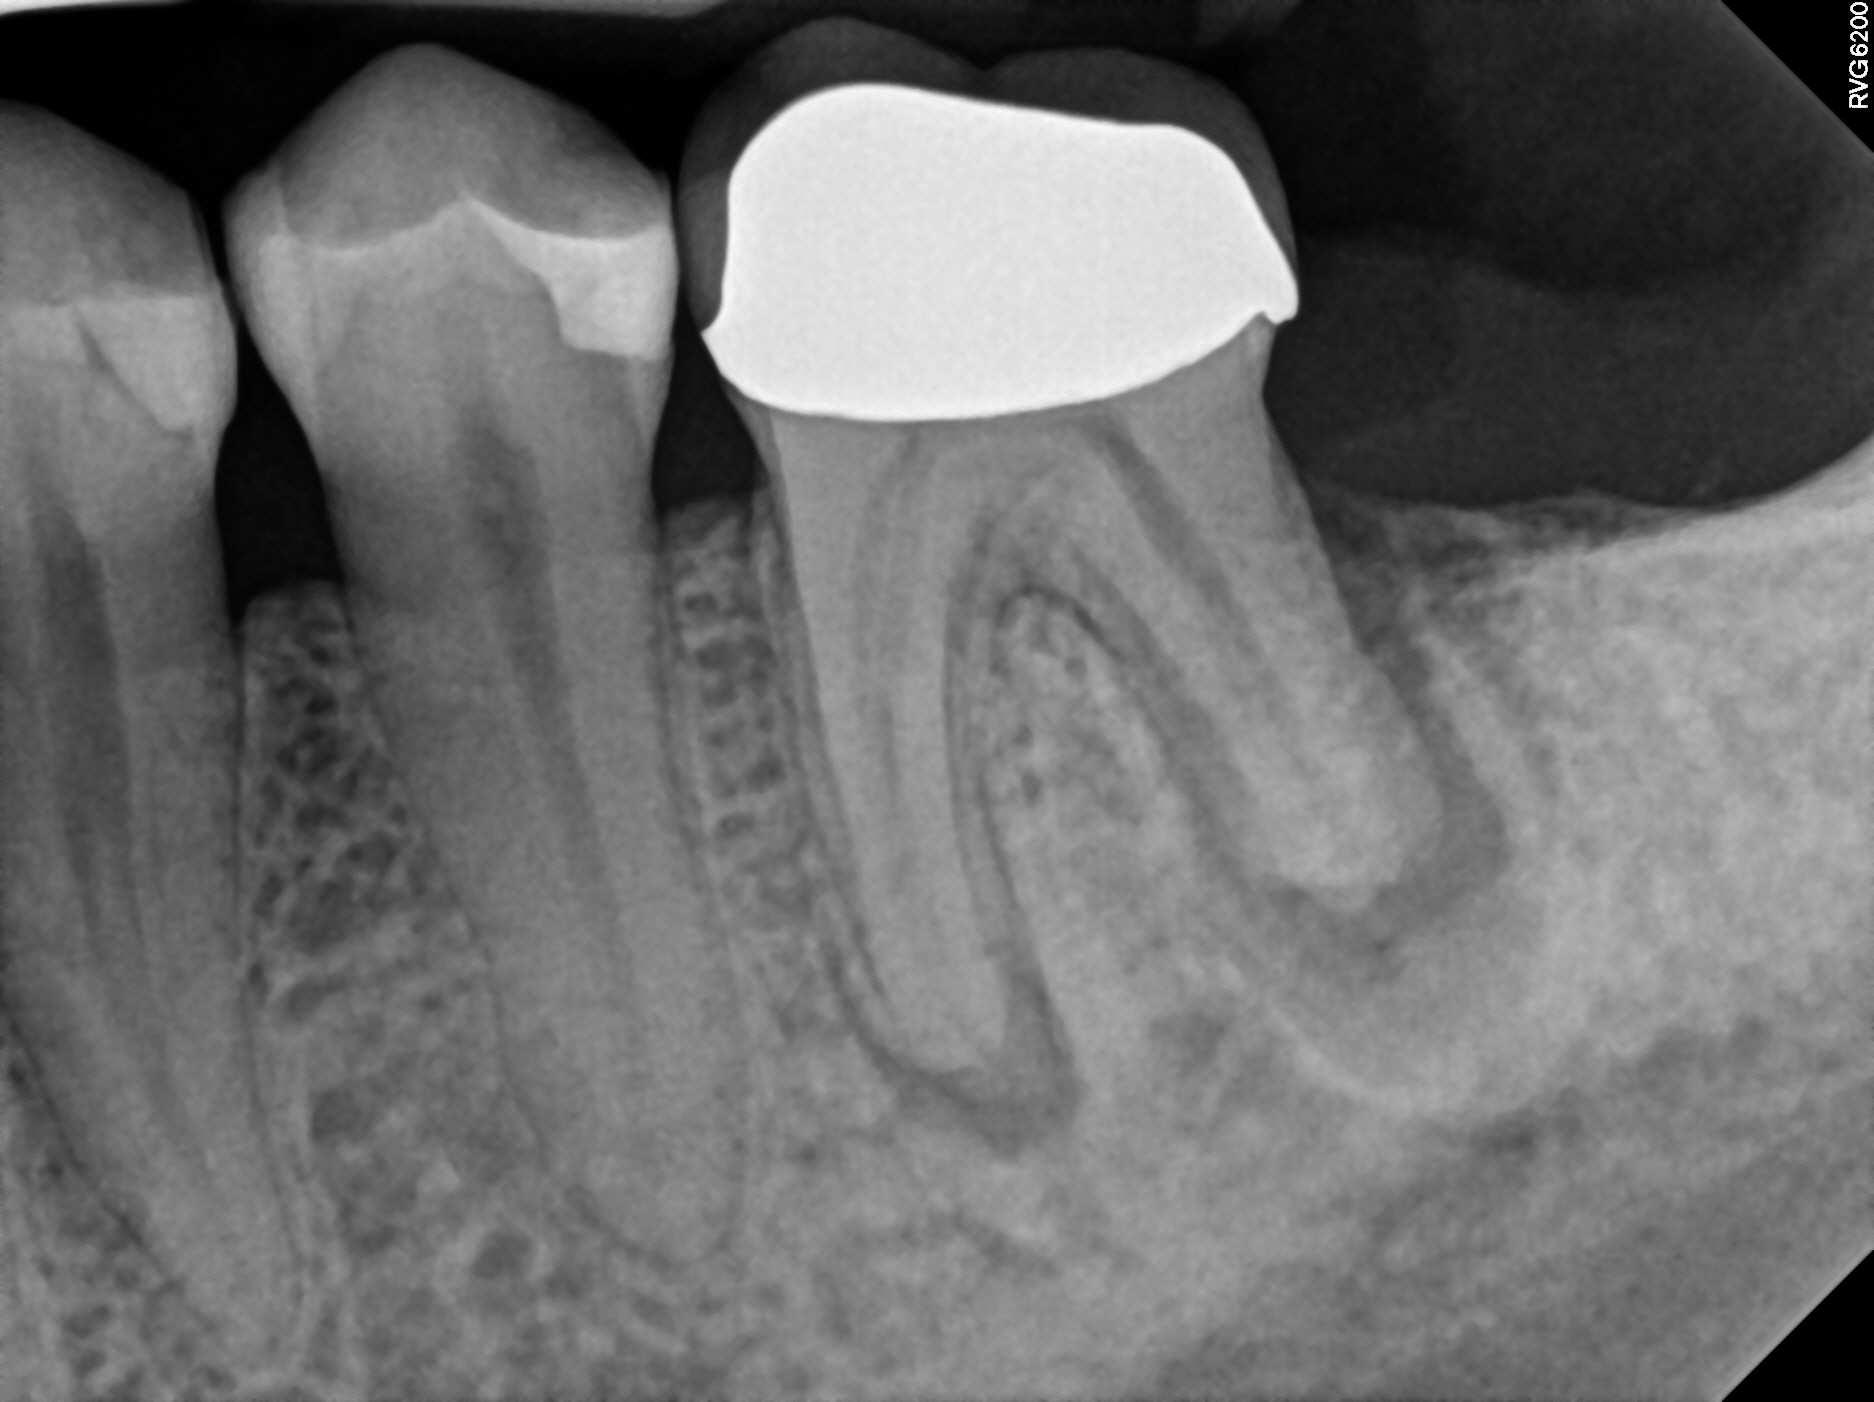

1_pre1

3_recall 4yr

Case 13

The left image is prior to treatment. This tooth became infected due to a crack in the tooth. The darker areas above the root tips is the abscess. A crown was placed to protect the tooth from cracking further. The right image is 4 years later--we can see complete bone healing.